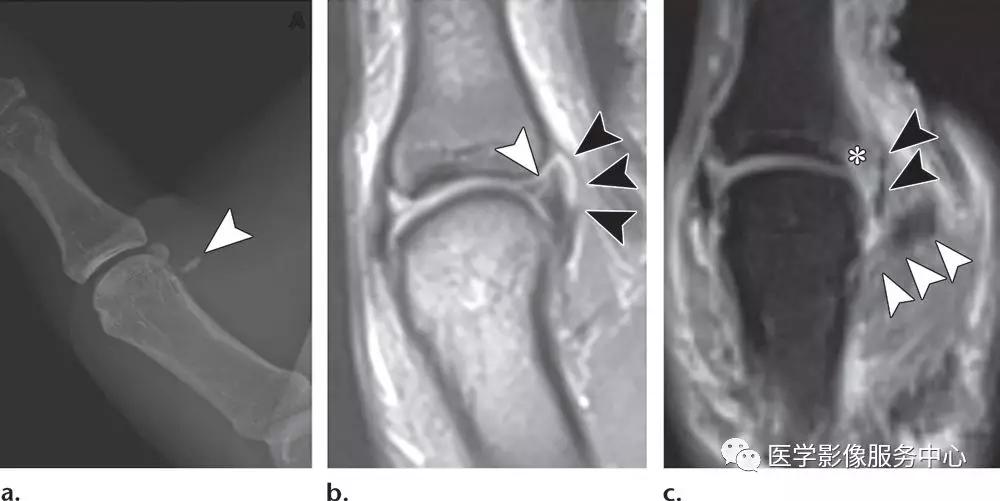

Mallet指:

(左)远端指骨背侧基底部末端伸肌腱插入处的小的撕脱骨片,伴轻微的远端指间关节屈曲。(右)软组织Mallet指,伸指总肌的终末肌腱的撕脱损伤,不合并撕脱骨折。

中央腱束撕脱:

伸指总肌的中央腱束的骨性撕脱,略示移位。合并轻度近端指间关节的过屈及远端指间关节的过伸,符合纽孔状畸形。